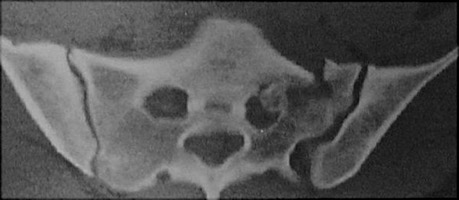

Sacral fractures occur commonly with other pelvic fractures as the result of major trauma. Transverse fractures (through the ala or arcades) result from directly applied forces to the sacrum. Vertical fractures occur as part of complex pelvic fractures. Stress fractures are usually vertical and near the sacroiliac joint. MRI or bone scan are useful to detect stress fractures. Sacral fractures can be quite subtle and are easily missed.

- Click on the image for a larger versionAAxial CT. This shows a comminuted fracture of the left side of the sacrum.